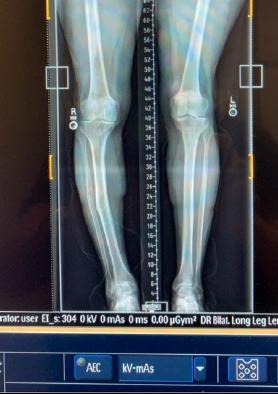

Before Surgery After Surgery